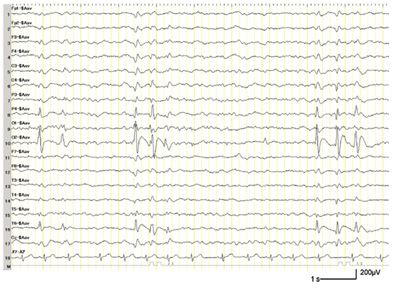

cognitivo, epilepsia o trastornos visuales. La epilepsia debida a

hipoglucemia neonatal tiene habitualmente una topografía occipital con

La prevalencia de la epilepsia del lóbulo

occipital en la encefalopatía hipoglucémica neonatal fue mayor del 50%,

siendo las características y el pronóstico a largo plazo mal conocidas

en la actualidad. La revisión presentada por H. Montassir y cols.

demuestra que la epilepsia del lóbulo occipital sintomática debida a

hipoglucemia neonatal es frecuentemente refractaria, con tendencia a

presentar estatus epiléptico en el transcurso de la enfermedad.Dr. José Uberos Fernández